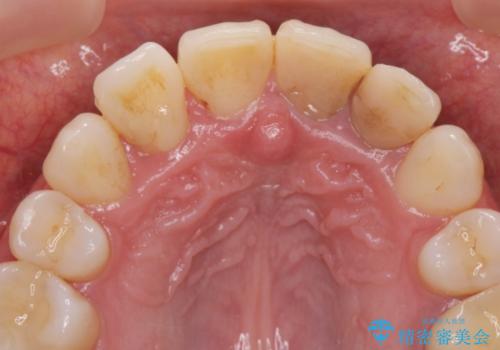

変色した歯を改善、セラミック治療

- 神経の死んでしまっている前歯の変色の改善を求めて来院されました。

根管治療をしたのち時間が経過して変色が目立つ歯と、レジン充填が複数箇所に及んでいる歯も同時にオールセラミック治療を行っていくこととなりました。

- 52.8万円(ジルコニアクラウン×4・仮歯×4)費用は治療当時の料金となります